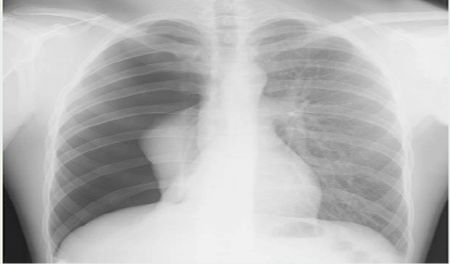

흉부 X-ray : 가장 일반적인 검사 방법으로 폐가 쪼그라든 정도를 확인.